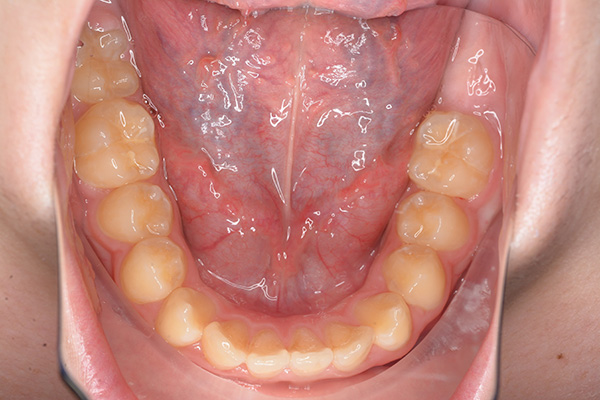

| 口腔内所見 | over jet 5.5mm,over bite 5.0mm,大臼歯関係はⅠ級 、Hellmanのdental ageはⅢBであり上突歯列を呈していた。 |

| パノラマ所見 | 上顎左右側犬歯は近心傾斜し側切歯歯根に重なるように認められた。 |